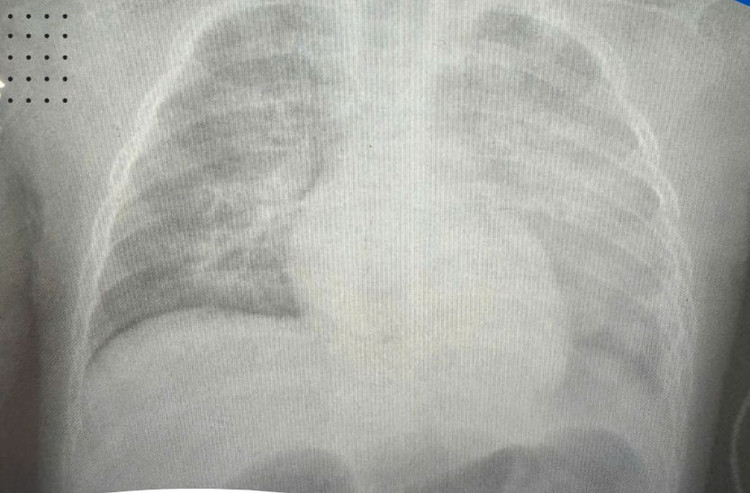

| Phim X-quang phổi bệnh nhi. Ảnh BVCC |

Chỉ sau 6 giờ nhập viện, kết quả chụp X-quang cho thấy cả hai lá phổi “trắng xóa” – dấu hiệu kinh điển của hội chứng suy hô hấp cấp (ARDS). Xét nghiệm khí máu của bệnh nhi cũng ở mức rất xấu.